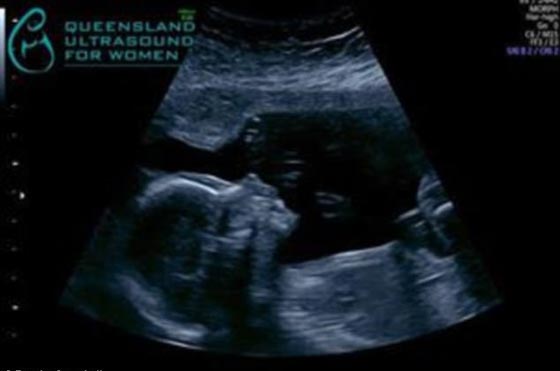

كامبل مع جنينها الذي فارق الحياة